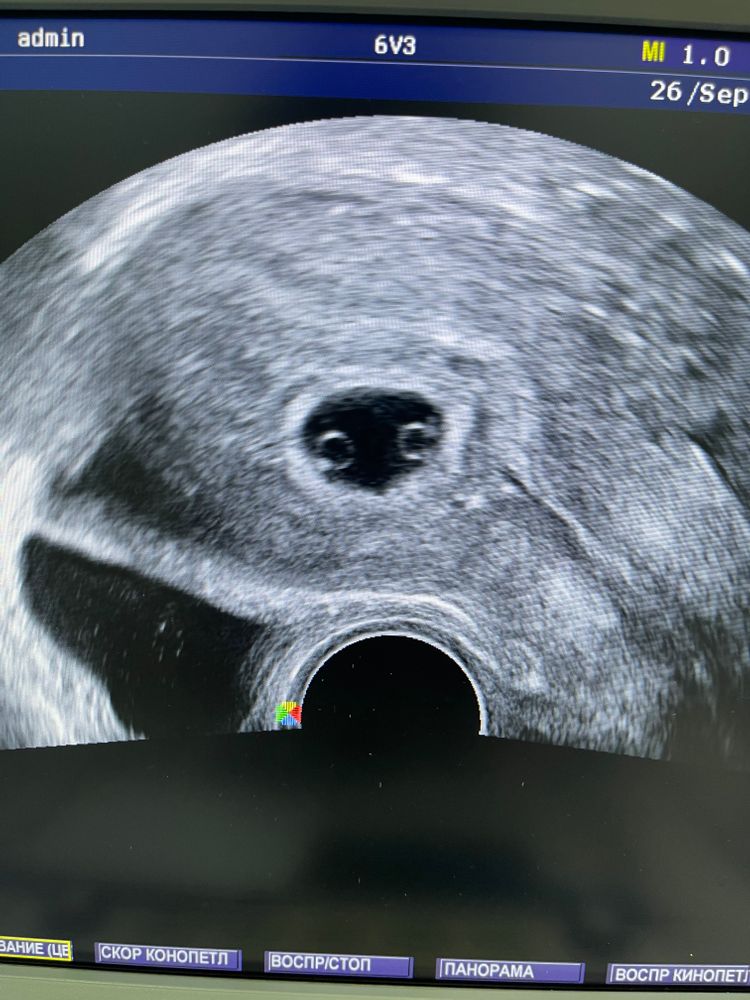

Удачное ЭКО🍀🙏

Ого! А по хгч и не скажешь, что двойня))) ну и сюрпризик)))

У меня хгч на 17дпп 6,5тысяч и один эмбрион да и то на 23дпп ктр у него 1,8мм всего, а у вас у каждого почти по 2см. Вы точно не ошиблись в размерах ктр? ну а вообще, конечно, раз такое дело, такая красивая картинка и история и сб + то это, безусловно, счастье! Легкой беременности и рождения в срок здоровых малышей 👍

Vera - будумамой, ой ктр я переписала как в выписке написано. Для меня это все впервой. 1-19мм а 2-1,8мм наверно в первом тоже 1,9. Спасибо большое 🍀

Круто как! И фотка с УЗИ такая смешная)). Растите здоровыми!

Вот наглядный пример, что хгч никак вообще не сообщит о многоплодной беременности👍